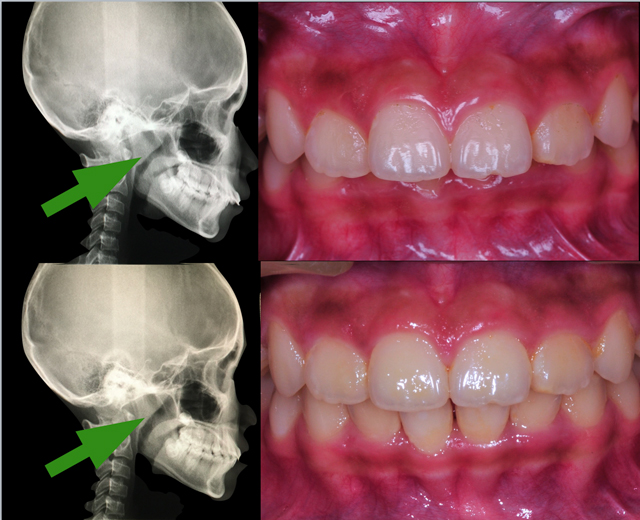

2 個月後第 3 次就診時,小女孩進步驚人,透過兒童隱形牙套上的特殊裝置引導下顎生長,後縮的小下巴變成正常下巴,深咬變成正常咬,不但準時吃完飯、功課也進步,媽媽在診間自責說「我愛她卻不知道用她的方式去理解她」,後來在半年多的療程中,小女孩因為齒顎矯正臉型改變,不止下巴出來了、連臉頰的蘋果肌也出現了。

矯正半年內,小女孩的臉型及笑容曲線明顯改變,蘋果肌與尖下巴也跑出來囉!